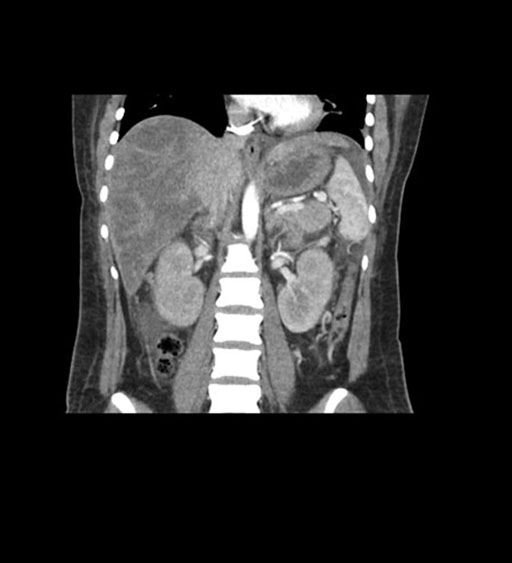

Coronal Arterial